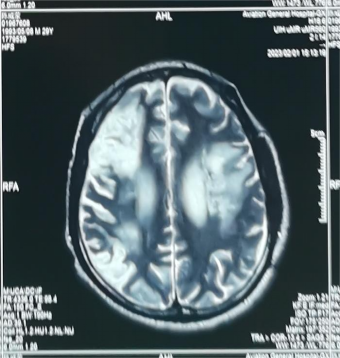

患者头颅磁共振